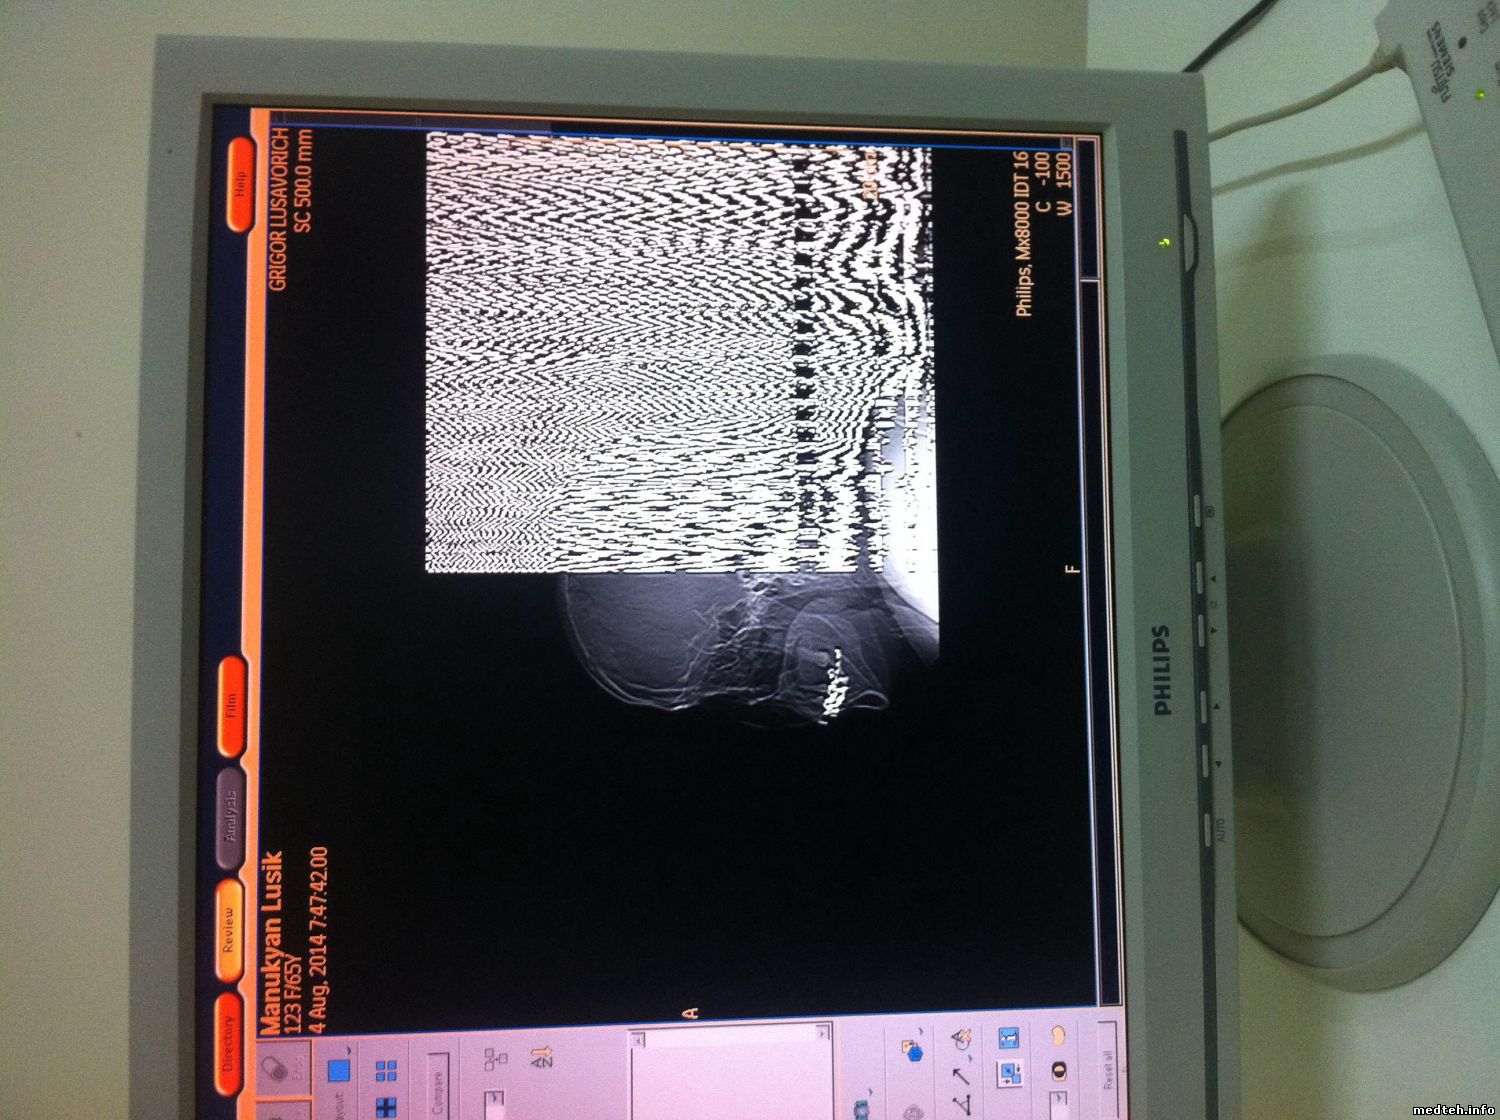

работаю с КТ Philips MX8000, вчера столкнулся с такой проблемой: После стандартной процедуре по включению аппарата на томограмме появились шумы в пол монитора, и круговые помехи на сканограме, после чего сделал калибровку по воздуху( раньше помогало ) но в этот раз не помогло а наоборот стало хуже интенсивность шумов на сканограме увеличелось, но на томограмме осталось прежнем.

вот снимки

4680378.jpg (178.3 Kb) · 5337631.jpg (196.1 Kb) · 9529230.jpg (209.1 Kb)